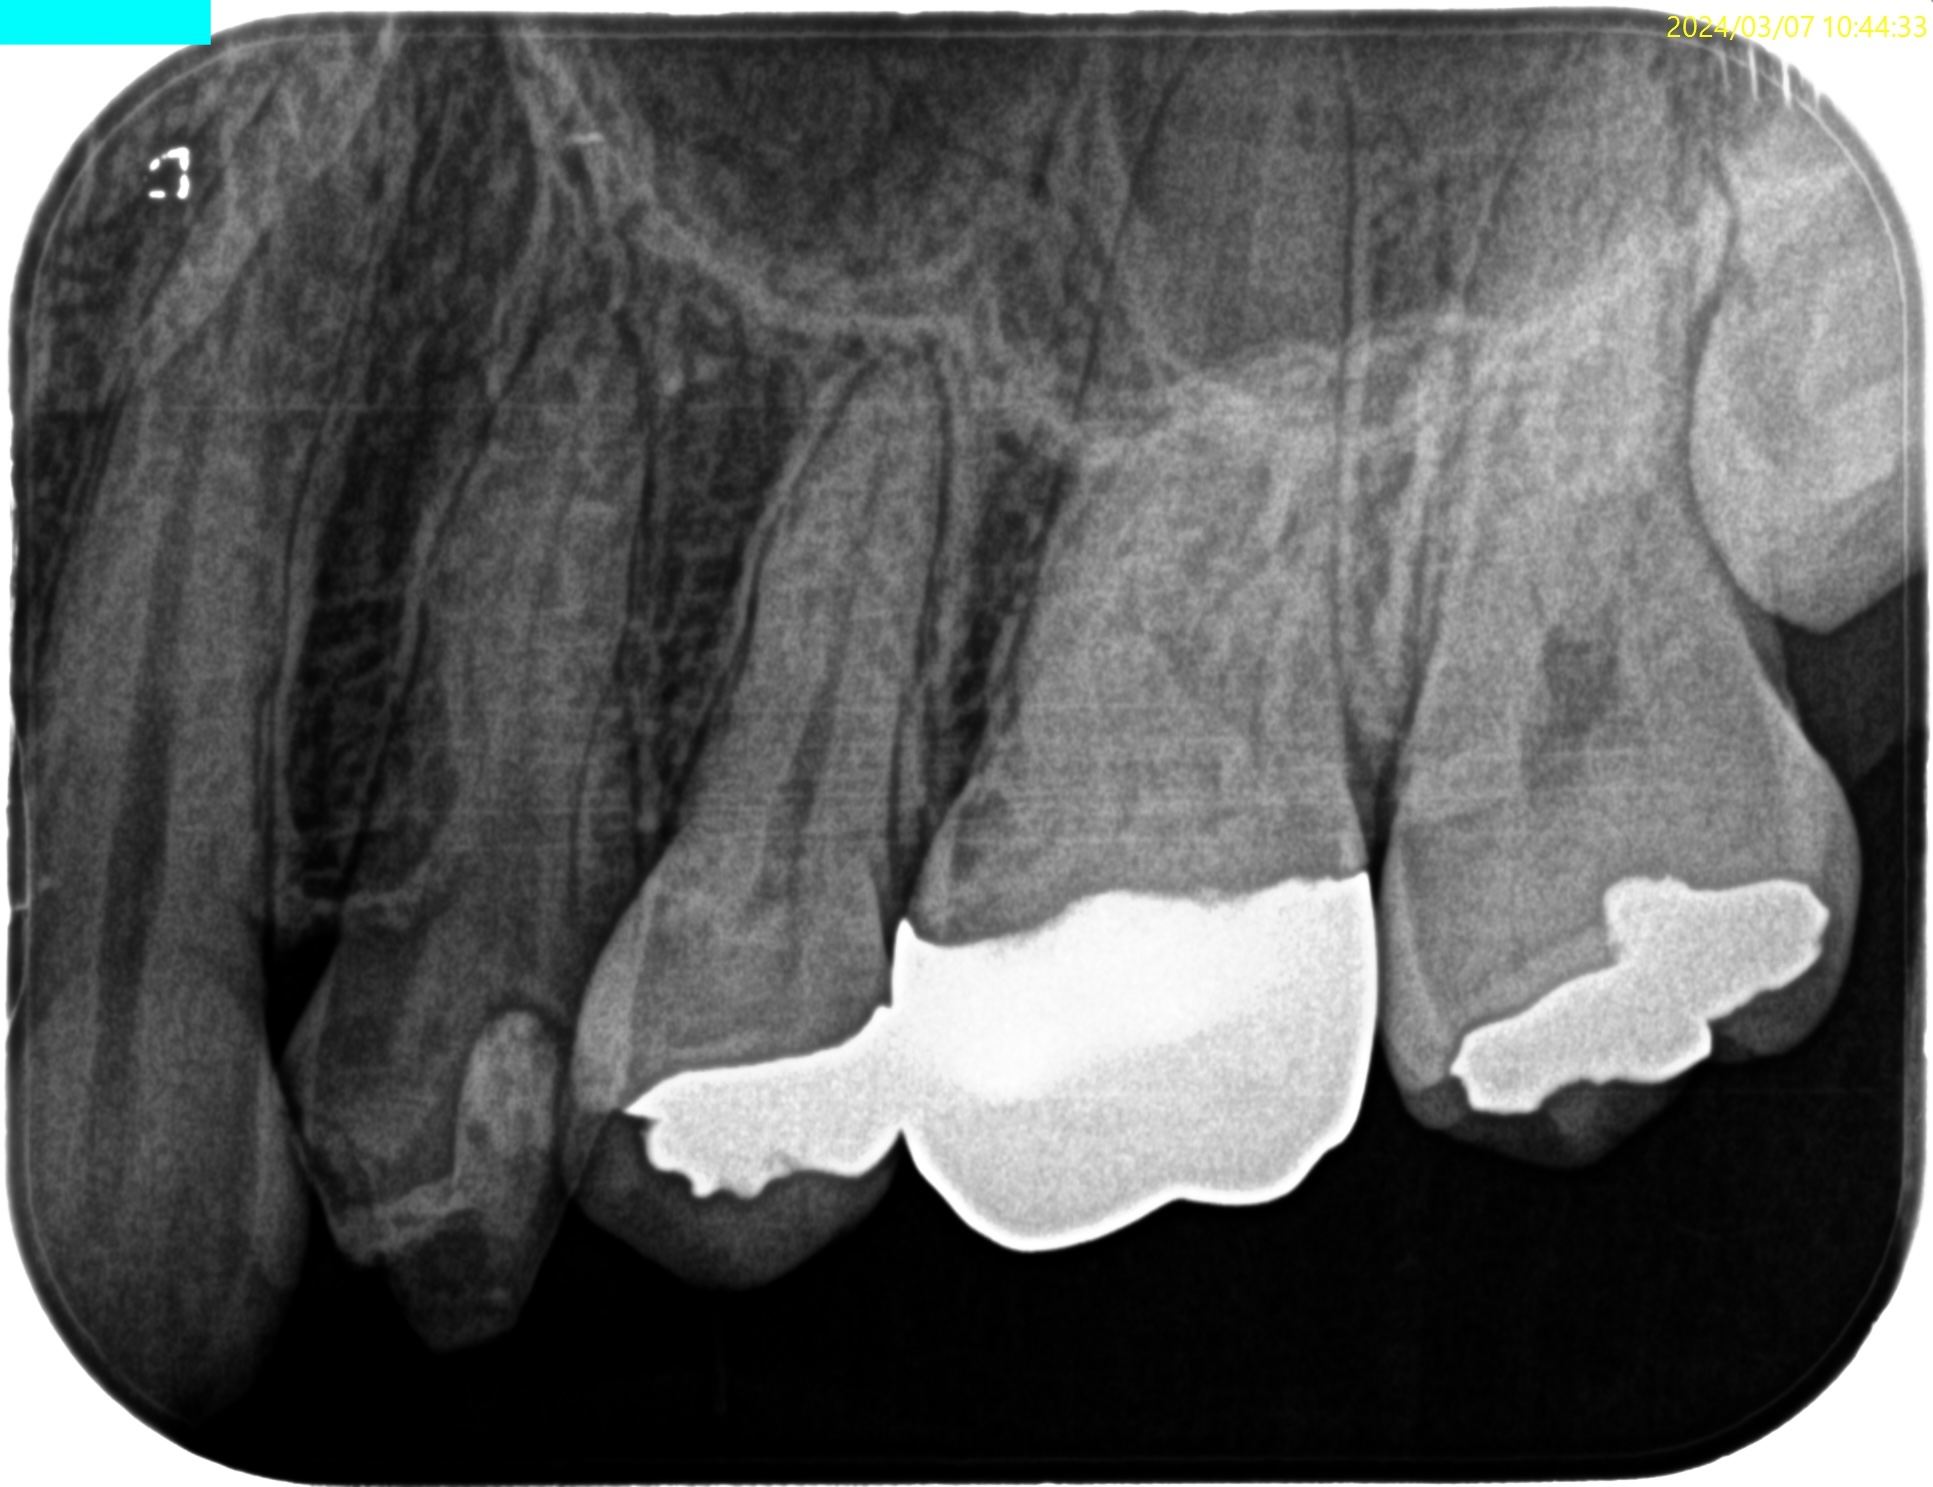

以下のようなケースでも可能なのだろうか?

私(当時Resident)も、

その後の二人のEndodontist(“自称”ではなく、“米国歯内療法学会”が認定する“Endodontist”である)も穿通させられなかったのだ。

何が言いたいか?と言えば、

全ての根管が穿通するとは限らない

ということである。

例えPAやCBCTで根管が見えていても、だ。